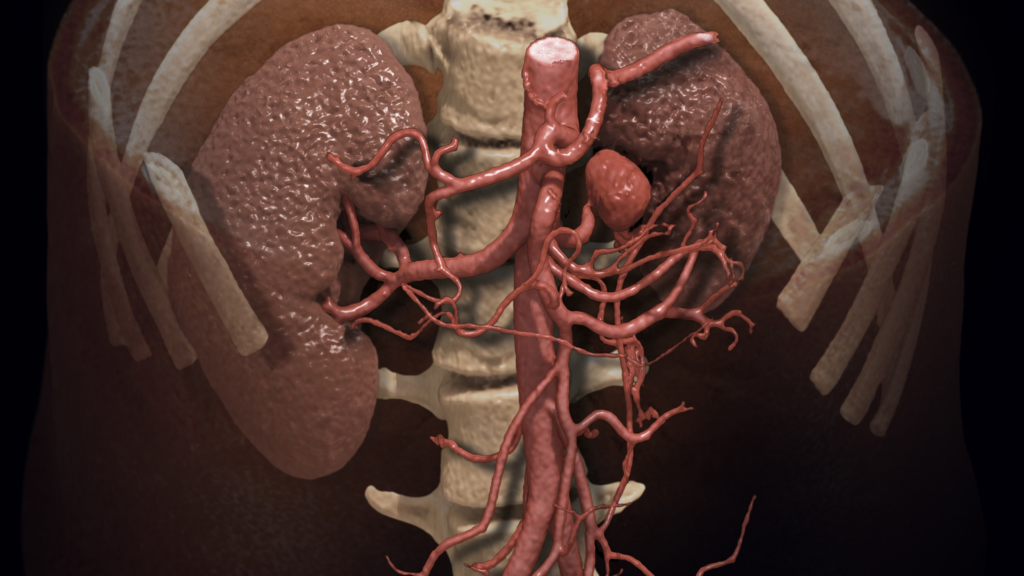

Cardiovascular

A full suite of advanced imaging workflows for CT, MR, XA, UL and PET/SPECT to facilitate assessment, diagnosis and treatment of diseases related to the heart and vessels.